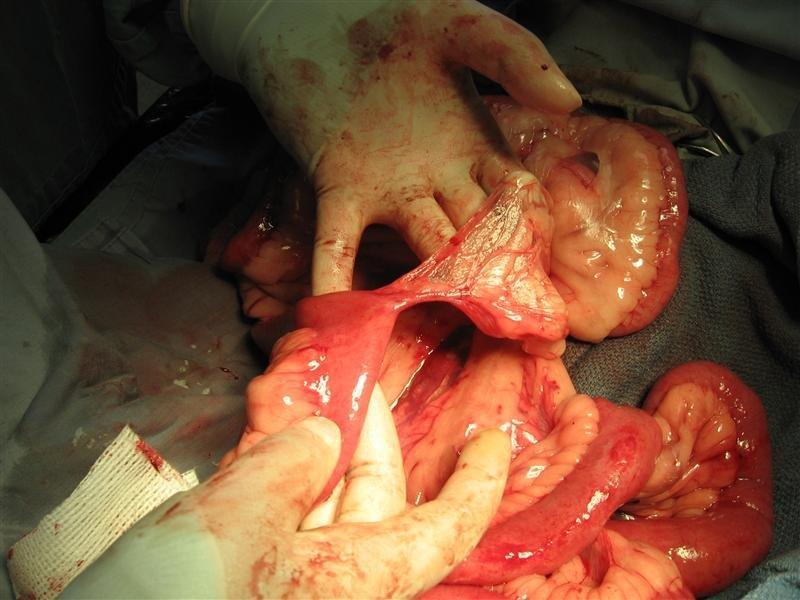

BHRR’s Barkley is healing just wonderfully from his obstruction surgery on April 1st and we continue to thank everyone who has assisted him to date with his BEGGING FOR BARKLEY Fundraiser! I am adding 2 pictures below from April 10th, 2010 and I have so many yet to put together for his slideshow. His sutures were subcutaneous yet you can see how well his incision is looking! Tonight, BHRR’s Barkley is going to help make a TON of homemade cinnamon buns; so that I can bring them into the Hospital with me tomorrow to THANK all the great staff that I work with that pulled together to save his life. It cannot be said enough, what a miracle story Barkley is! He could really use some more financial support to finish paying off his extensive Vet/Rehab Bills and on behalf of BHRR’s Barkley, I humbly thank everyone in advance for your consideration.

BHRR’s Barkley (2.5+) – April 10th, 2010

Since you have now seen the inside of BHRR’s Barkley, let me informally introduce you to the outside of BHRR’s ‘Honourary’ Great Dane, BHRR’s Barkley, the newest addition to BHRR! His coat is really dry, flaky plus dull and he needs a lot more muscle toning BUT he is one gorgeous boy. I cannot wait to see how he looks in a few weeks time! Please consider helping BHRR’s Barkley by donating to his “BEGGING FOR BARKLEY” Fundraiser.

BHRR’s Barkley(2.5+ years of age) – April 1st – post – op at BHRR with Sean & BHRR’s Barkley – April 2nd – 1st day post-op